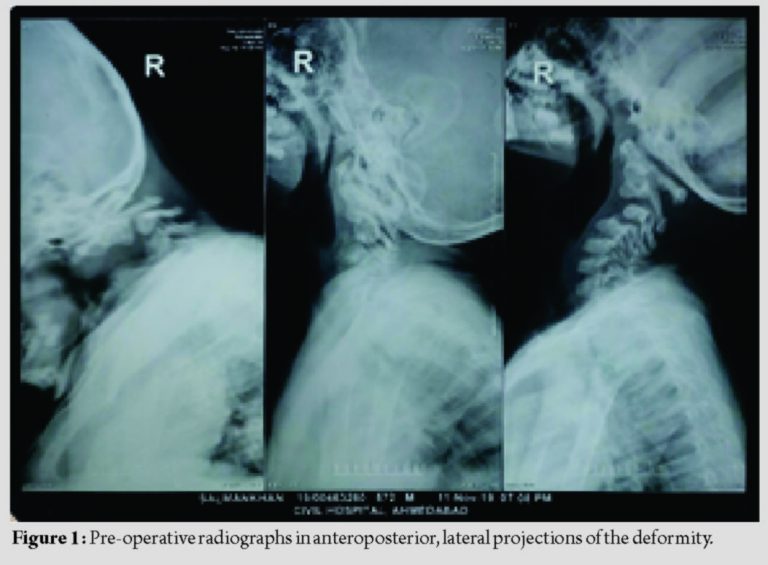

Cervical X-rays with lateral projection (Fig. 1) were done which showed C3 hemivertebrae resulting in significant kyphosis of the cervical spine posterior facet subluxation with increased interspinous widening. Mean sagittal Cobb’s angle was 35° which corrected to 5° postoperatively (Fig. 2). MRI was done which showed significant compression at C3 level with canal diameter of 4.7 mm with myelomalacia (Fig. 3) which were hyperintense on T2-weighted images and hypointense on T1. Dynamic and static (Fig. 4) 3D computed tomography (CT) scan were done preoperatively to understand the bony anatomy, flexibility of the kyphosis, and course of vertebral artery and to plan the bony anchors and instrumentation.